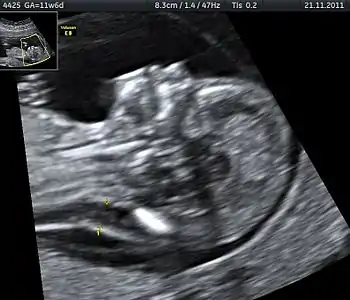

Nuchal scan (NT procedure) is performed between 11 and 14 weeks of gestation, because the accuracy is best in this period. The scan is obtained with the fetus in sagittal section and a neutral position of the fetal head (neither hyperflexed nor extended, either of which can influence the nuchal translucency thickness). The fetal image is enlarged to fill 75% of the screen, and the maximum thickness is measured, from leading edge to leading edge. It is important to distinguish the nuchal lucency from the underlying amniotic membrane.[8]

Normal thickness depends on the crown-rump length (CRL) of the fetus. Among those fetuses whose nuchal translucency exceeds the normal values, there is a relatively high risk of significant abnormality.

The translucent area measured (the nuchal translucency) is only useful to measure between 11 and 14 weeks of gestation, when the fetal lymphatic system is developing and the peripheral resistance of the placenta is high. After 14 weeks the lymphatic system is likely to have developed sufficiently to drain away any excess fluid, and changes to the placental circulation will result in a drop in peripheral resistance. So after this time any abnormalities causing fluid accumulation may seem to correct themselves and can thus go undetected by nuchal scanning.